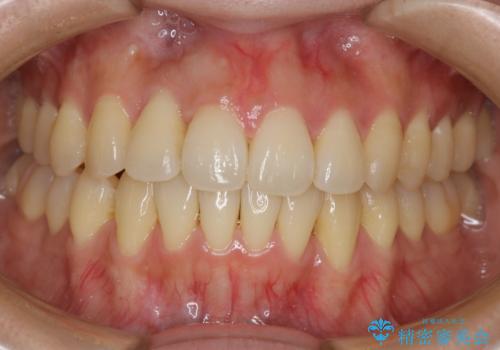

[ 総合歯科診療 ] がたつきの改善とセラミック治療

![[ 総合歯科診療 ] がたつきの改善とセラミック治療の症例 治療前](https://seimitsushinbi.jp/wp/wp-content/uploads/2024/03/f0f438a14c56b185411649f48b5b188c-500x350.jpg?v=1710833163)

![[ 総合歯科診療 ] がたつきの改善とセラミック治療の症例 治療後](https://seimitsushinbi.jp/wp/wp-content/uploads/2024/03/7212917eb9c4ef33050c52e7f9724490-500x350.jpg?v=1710833188)